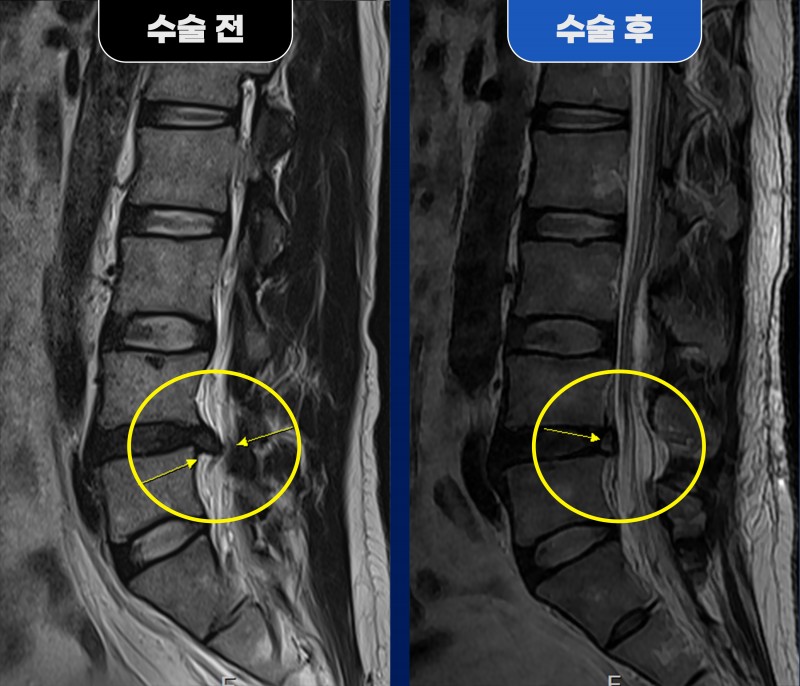

■ Before (수술 전) 38세 남성 환자분께서 심한 좌측 다리 방사통을 주소로 내원하셨습니다. MRI 검사 결과, 요추 4번 / 5번(L4/5) 부위에서 좌측 추간판 탈출증이 확인되었으며, 동시에 우측 추간공 협착증이 함께 동반된 상태였습니다. 문제는 디스크 제거 수술 시, 파열된 디스크 안쪽까지 과도하게 제거할 경우 오히려 우측 추간공 간격이 더 좁아질 수 있는 위험 요소가 있다는 점이었습니다. 하지만 환자분께서는 우측 다리 증상은 거의 없는 상태였기 때문에, 우측 구조물을 최대한 보존하면서 좌측 증상을 유발하는 디스크만 정확히 제거하는 양방향 내시경을 통한 좌측 추간판 제거술을 계획하게 되었습니다. ■ After (수술 후) 수술 중 좌측 신경은 파열된 디스크에 의해 심하게 눌려 부종과 충혈 소견이 확인되었습니다. 이에 해당 디스크 조각과 압박 원인을 제거하고 신경을 충분히 감압해 주었습니다. 수술 후 MRI에서는 파열된 추간판이 중앙에서 좌측까지 깨끗하게 제거된 모습이 확인되었으며, 특히 흥미로운 점은 수술 전 협착되어 있던 우측 추간공 공간이 자연스럽게 넓어진 변화가 관찰되었다는 점입니다. 이는 통증의 주요 원인이 제거되면서 과도하게 긴장되어 있던 척추 주변 근육의 긴장이 풀리고, 디스크 간격(높이)이 회복되면서 자연스러운 공간 복원이 이루어진 결과로 볼 수 있습니다. 환자분은 수술 후 좌측 다리 방사통이 현저히 감소하였고, 빠른 일상 복귀가 가능할 정도로 회복되었습니다. 청담해리슨송도병원은 단순히 병변만 제거하는 치료가 아닌, 척추 전체의 균형과 기능 회복까지 고려한 정밀 내시경 수술을 통해 환자의 회복 속도와 치료 결과를 함께 높이고 있습니다. |